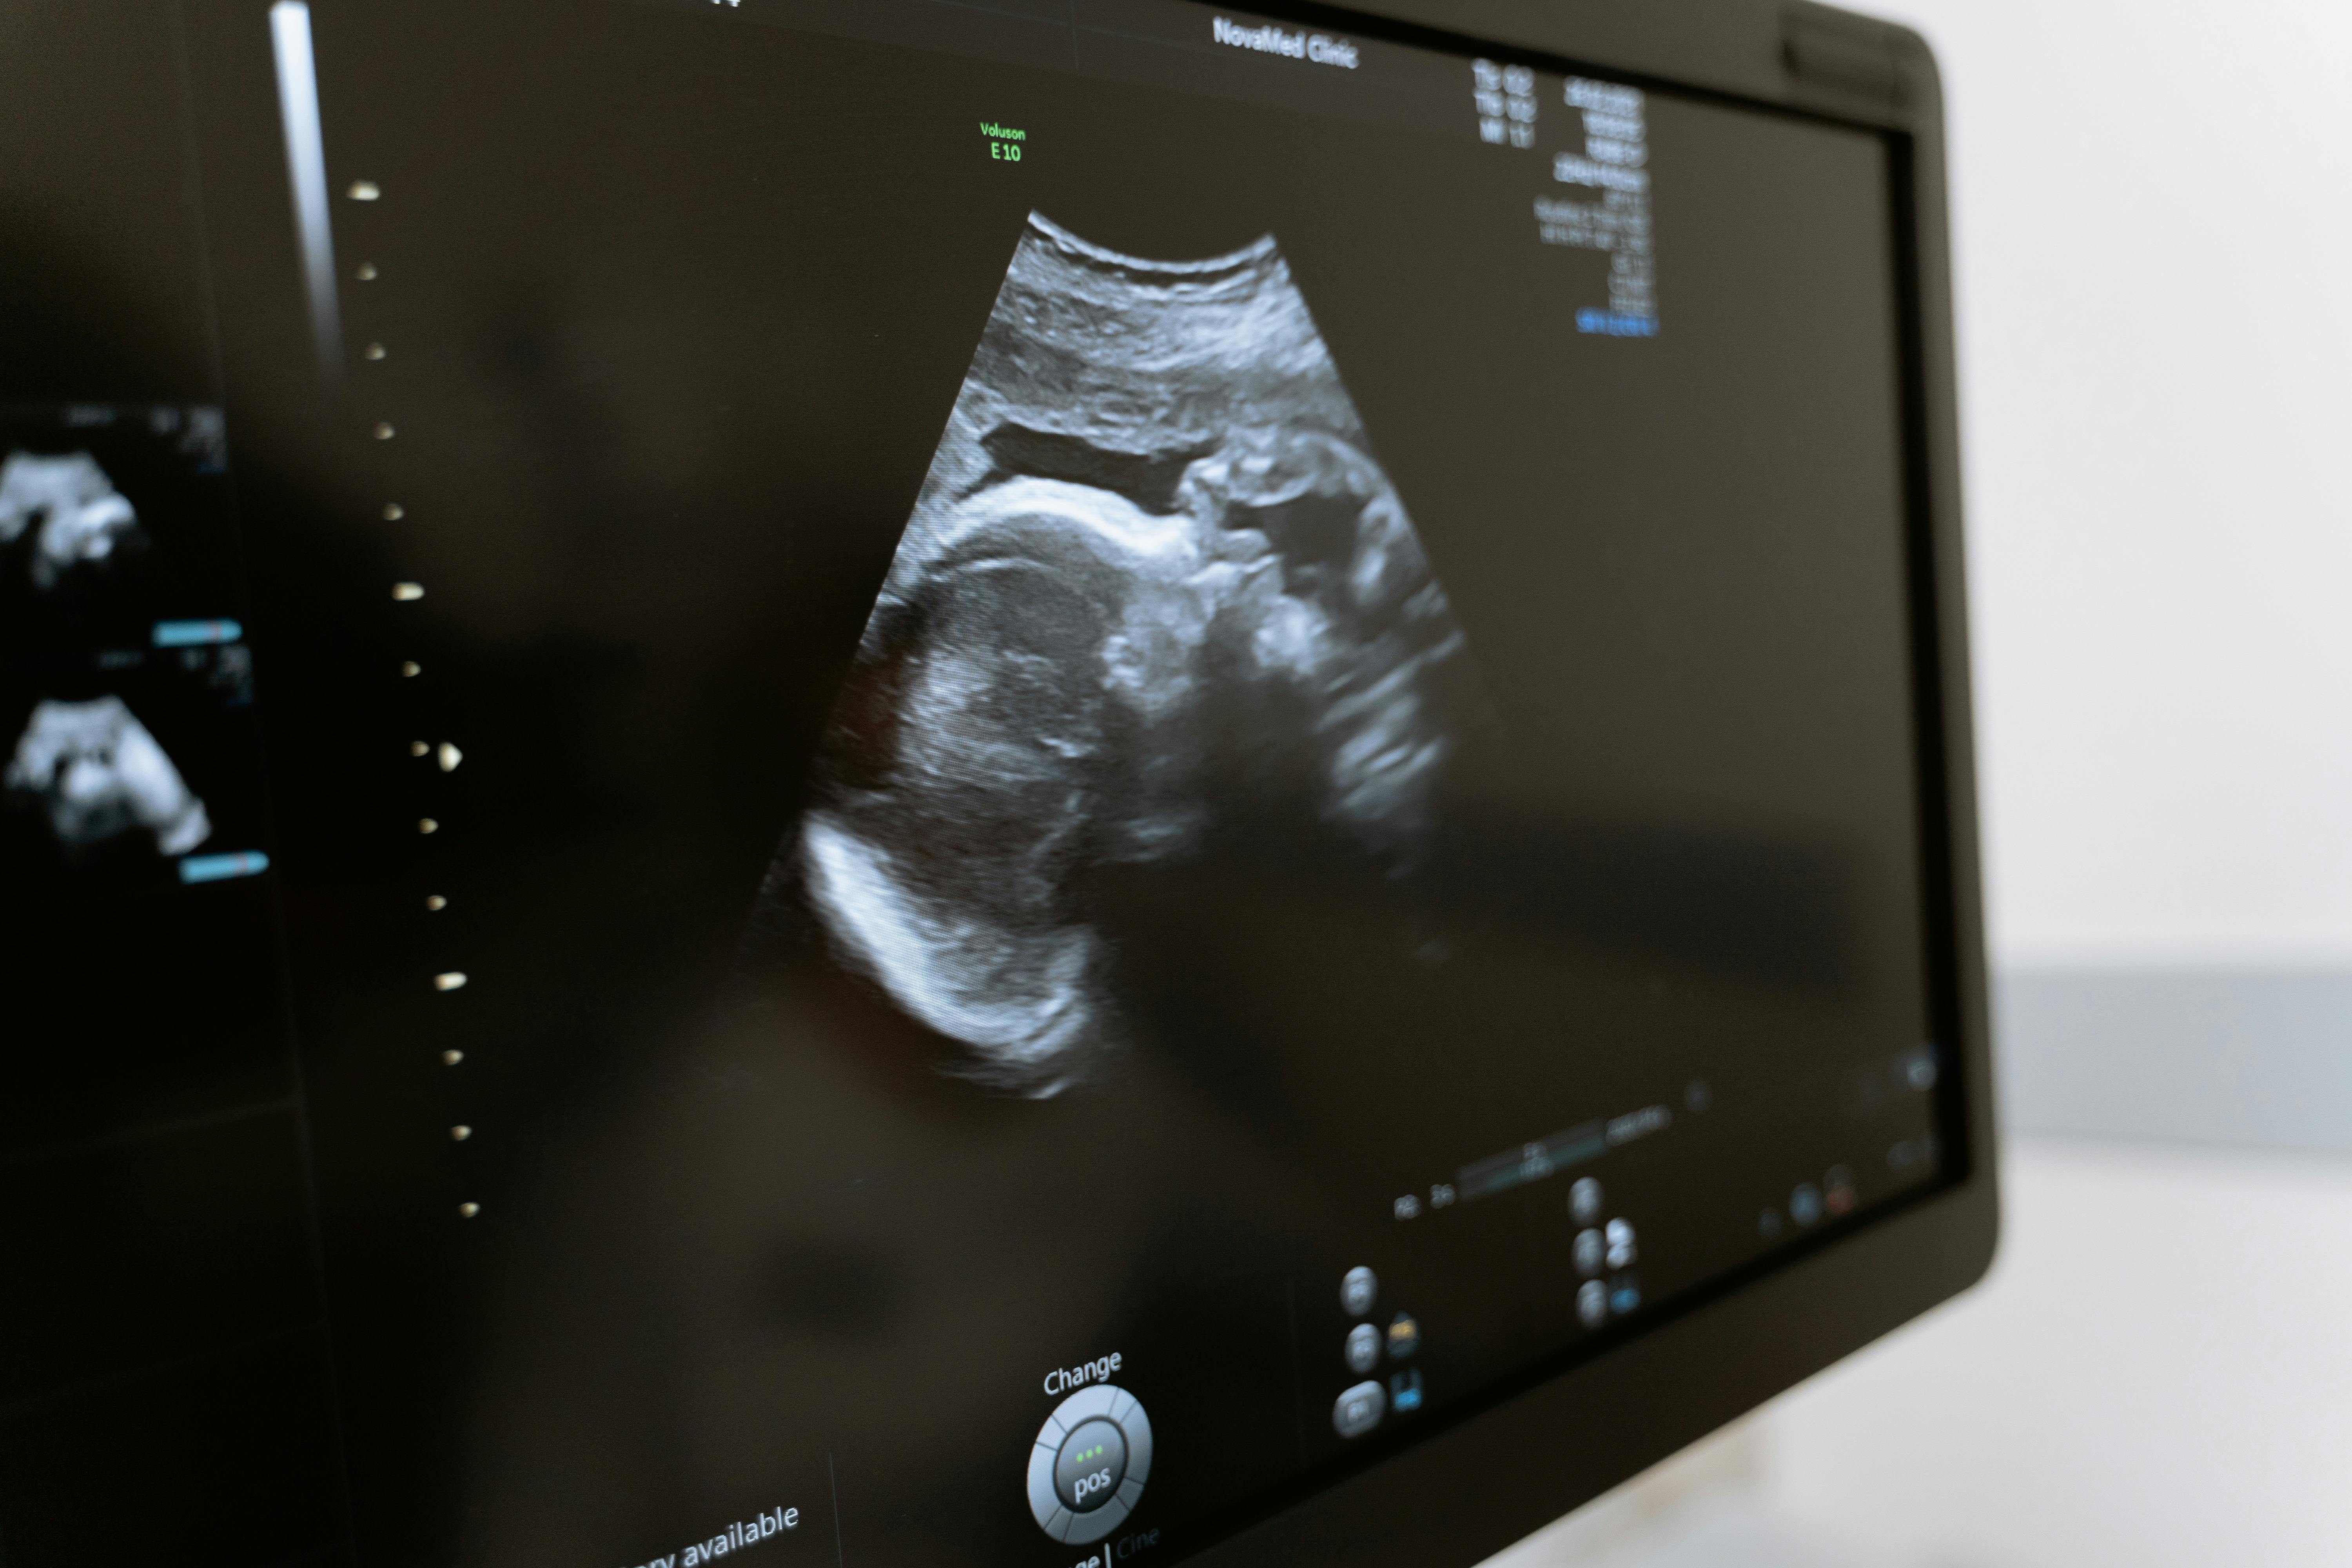

Cornell University researchers have developed a new device that could make fertility treatments faster and easier by automating a delicate step in the process called oocyte cumulus removal. This step is needed to separate the protective cells around an egg before fertilization, a task that usually requires skilled hands and careful attention. Mistakes during this step in IVF treatments can damage eggs and reduce the chances of a successful pregnancy, which makes it a critical part of in vitro fertilization procedures.

Traditionally, fertility clinics perform this step in IVF treatments by manually moving each egg with tiny pipettes to remove the surrounding cells. The process takes time, relies on trained staff, and carries a risk of error. The new device, a disposable chip that uses vibration, creates a swirling flow that separates the smaller cumulus cells from the larger eggs automatically. This innovation allows the procedure to be done more quickly and with less risk of damaging the eggs.